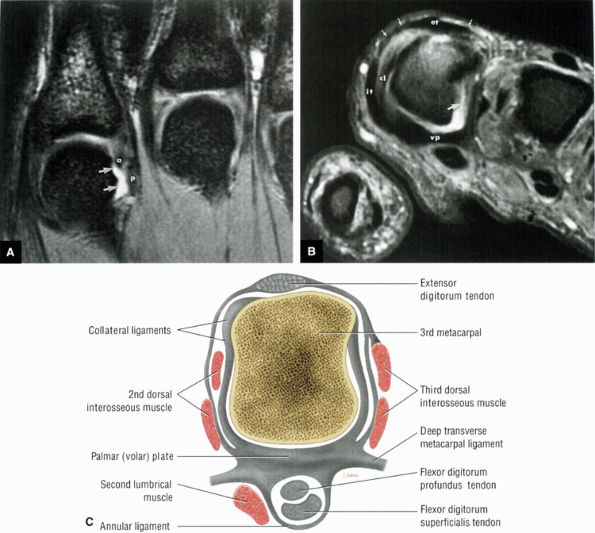

FIGURE 10.31 ● Normal coronal anatomy. (A) Fatty atrophy or denervation of the thenar muscles raises the possibility of median neuritis, and in such cases the median nerve is closely examined for enlargement or increased signal. (B) Tenosynovitis of the flexor tendons with fluid in the tendon sheaths can occasionally cause enough mass effect on the median nerve to cause median neuritis. (C) The first carpometacarpal joint (the articulation between the trapezium and the base of the first metacarpal) is a common location for degenerative arthrosis, often visualized at the corner of a coronal image. (D) Fluid in the pisotriquetral recess is a common finding. In the absence of other findings such as degenerative changes at the joint, a small amount of fluid in the pisotriquetral recess is probably of no significance. (E) Fractures of the distal scaphoid extending to the articular surface should be characterized as entering the lunate fossa (the radial articulation with the lunate) or the scaphoid fossa (the radial articulation with the scaphoid). Such articular extension, particularly if depressed or displaced, can lead to significant radiocarpal degenerative disease. (F) The triscaphe joint consists of the distal pole of the scaphoid articulating with the trapezoid and trapezium and is considered the second most common site of wrist arthrosis. (G) The proximal row should normally form a continuous smooth convex curve. Any subtle offset of the triquetrum from the lunate, or the scaphoid from the lunate, is suggestive of a tear of the lunotriquetral or scapholunate ligaments. (H) The triangular fibrocartilage attachment to the radius may attach to hyaline articular cartilage, and it is important not to mistake the gray cartilage signal at the attachment for a tear, which is usually of fluid signal intensity. (I) The proximal pole of the hamate may occasionally articulate with a normal variant type II lunate facet located on the distal ulnar aspect of the lunate. When this occurs, degenerative changes are visualized at the hamate-lunate articulation in almost half of cases. (J) Small degenerative perforations in the membranous component of the scapholunate ligament are not uncommon in older patients, and in this population they may be asymptomatic and unassociated with carpal instability. (K) The TFC has insertions at the tip and at the base of the ulnar styloid. Therefore, fractures at the base of the ulnar styloid may disrupt the integrity of the TFC and potentially cause distal radial ulnar joint instability. (L) On coronal images through the dorsal wrist, the dorsal component of the scapholunate ligament may occasionally be discretely identified. The dorsal component is considered the most important of the scapholunate ligament components for maintaining carpal stability. (M) Another significant and commonly overlooked location for degenerative arthrosis is at the base of the third metacarpal, where a common protuberance, called a carpal boss, articulates with the capitate. Unusually prominent carpal bosses may become hypertrophic and articulate with a spur on the distal capitate, which can often be palpated by the patient as a tender bump just beneath the skin along the dorsal wrist. (N) Ganglion cysts can be visualized extending through the dorsal capsular ligaments on coronal images through the dorsal wrist. Common sites of origin are the scapholunate ligament, the triscaphe joint, and the third carpometacarpal joint (often associated with degenerative change at a carpal boss).

|

FIGURE 10.32 ● Normal axial anatomy. (A) Fractures of the hook of the hamate, commonly occult on plain films, are easily visualized on axial MR images through the hamate. (B) The flexor carpi radialis is visualized cradled by the hook of the trapezium. This is a common location for tenosynovitis and tendinosis of the flexor carpi radialis tendon. (C) The thenar muscles (abductor and flexor pollicis brevis) are visualized volar to the radial aspect of the distal carpus. Median neuritis should be suspected when selective fatty atrophy or denervation of the thenar muscles is visualized. (D) The median nerve within the carpal tunnel may display evidence of median neuritis, such as increased signal or enlargement. A mass lesion of the carpal tunnel at this level may cause mass effect within the carpal tunnel and impinge the median nerve. (E) The pisotriquetral joint is a common location for severe degenerative arthritis and synovitis, associated with significant ulnar-sided pain. (F) The extensor pollicis longus crosses obliquely dorsal to the extensor pollicis longus and brevis tendons. This is a not uncommon location for tears of the extensor pollicis longus tendon. (G) The scapholunate articulation is a common location for ganglion cysts, usually found directly dorsal to the scapholunate ligament. Even small dorsal ganglion cysts in this location can be exquisitely tender and painful. Often, a small neck of fluid signal extends from the dorsal ganglion cyst back toward the scapholunate ligament, and in certain cases a small perforation of the scapholunate ligament can be suggested. (H) The extensor pollicis brevis and abductor pollicis longus tendons are located lateral to the distal radius. Tendinosis and tenosynovitis of these tendons is known as de Quervain's stenosing tenosynovitis. (I) Not uncommonly the extensor carpi ulnaris tendon is subluxed over the ulnar styloid, particularly when the patient is supinated, with the ulnar styloid pointing dorsally. This is not necessarily an abnormal finding, particularly when the extensor carpi ulnaris tendon otherwise appears normal. (J) The triangular shape of the TFC complex is best appreciated on axial images, with the apex of the triangle attaching at the ulnar styloid and the broader base of the triangle attaching at the radius. (K) The distal radioulnar joint is examined in the axial plane to view the alignment of the radius with respect to the ulna. The ulna lies within the concave groove in the medial aspect of the radius called the sigmoid notch, and the two bones lie grossly in the same plane. Mild apparent dorsal shift of the ulna with respect to the radius is normal when the wrist is scanned in full pronation (the ulnar styloid pointing ulnar-volar). (L) When the triangular fibrocartilage is torn, or if there is a displaced fracture at the base of the ulnar styloid, the distal radial ulnar joint may become somewhat destabilized, ultimately resulting in degenerative arthrosis and synovitis. Another cause of distal radioulnar joint degenerative change is the ulnar impingement syndrome, in which a short ulna erodes the ulnar aspect of the distal radius.